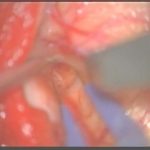

摘出 中